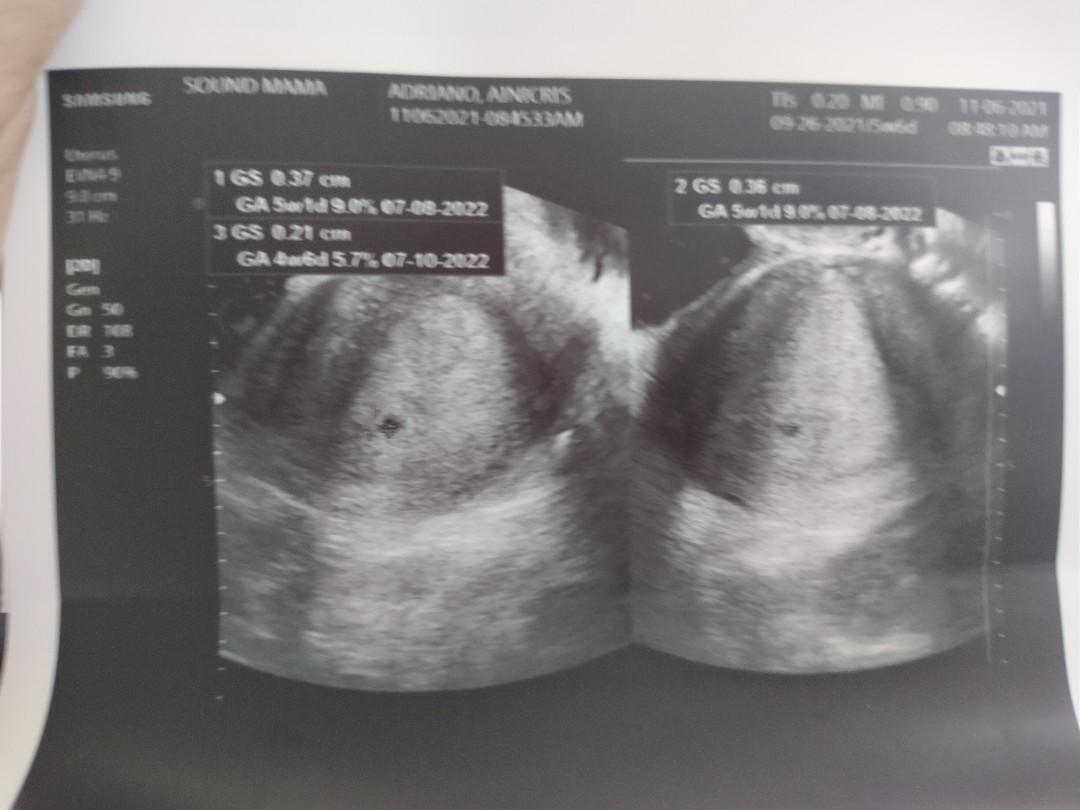

5 weeks ♥️

Sabi ng ob ko, wala pa daw baby sa tummy ko but normal lng daw kasi 5weeks palang naman at may sapot na daw na nagiindicate na pregnant talaga ko. After 2weeks may follow up check up ako and trans v ulit, worried ako mga mamsh ☹️ ganun po ba talaga pag 5weeks palang ??

eto po baby ko nung 5 weeks hehehe ngayon ang laki and likot na nya. normal lang po yan. doble ingat po 🥰